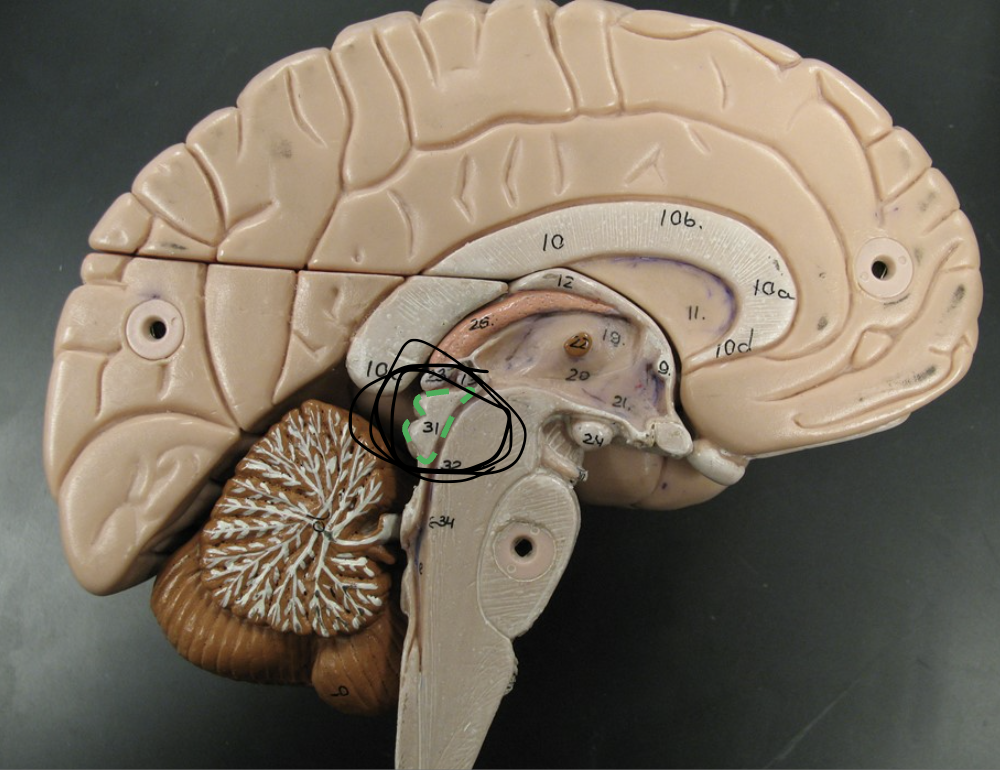

What does the circle indicate, and what is its function?

The Midbrain

Responsible for processing auditory and visual information, as well as motor control.

*Inferior (below) diencephalon

what does the circle indicate?

Tectum part of the midbrain

involved in auditory and visual reflexes, containing the superior and inferior colliculi.

What are the 4 bulges posterior from the tectum called? (You only see 2 because this is a sagittal section.)

Corpora quadrigemina